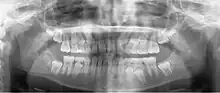

Panoramic radiograph

A dental panoramic radiograph, showing the maxilla and mandible, all the teeth including the "wisdom teeth," the frontal and maxillary sinuses, the nasal cavity and the temporomandibular joint and other near by head and neck anatomy.